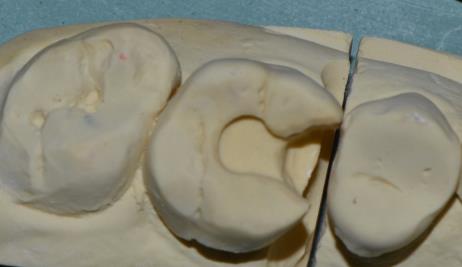

嵌體(ti) 取模

嵌體(ti) 加工製作成各種樣子